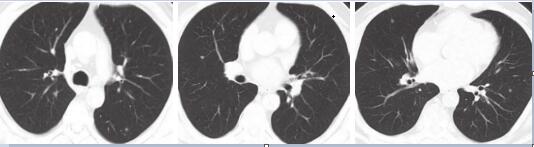

入院后完善基线检查,2015-11-04完善颈部增强CT及MRI检查:下咽部治疗后改变,双侧颈部、左锁骨上淋巴结肿大(图2)。胸腹盆增强CT示双肺多发小结节(图3)。

图3 胸腹盆增强CT可见双肺小结节